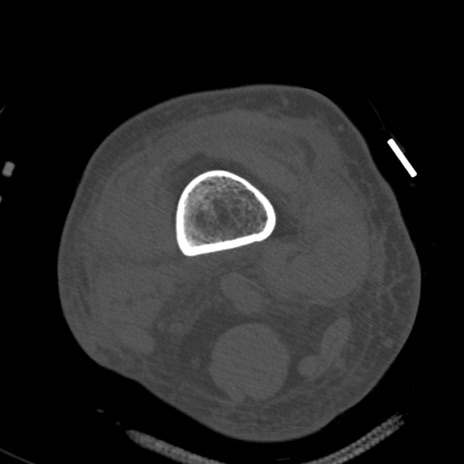

症例28 右膝関節CT(横断像)

右膝関節CT